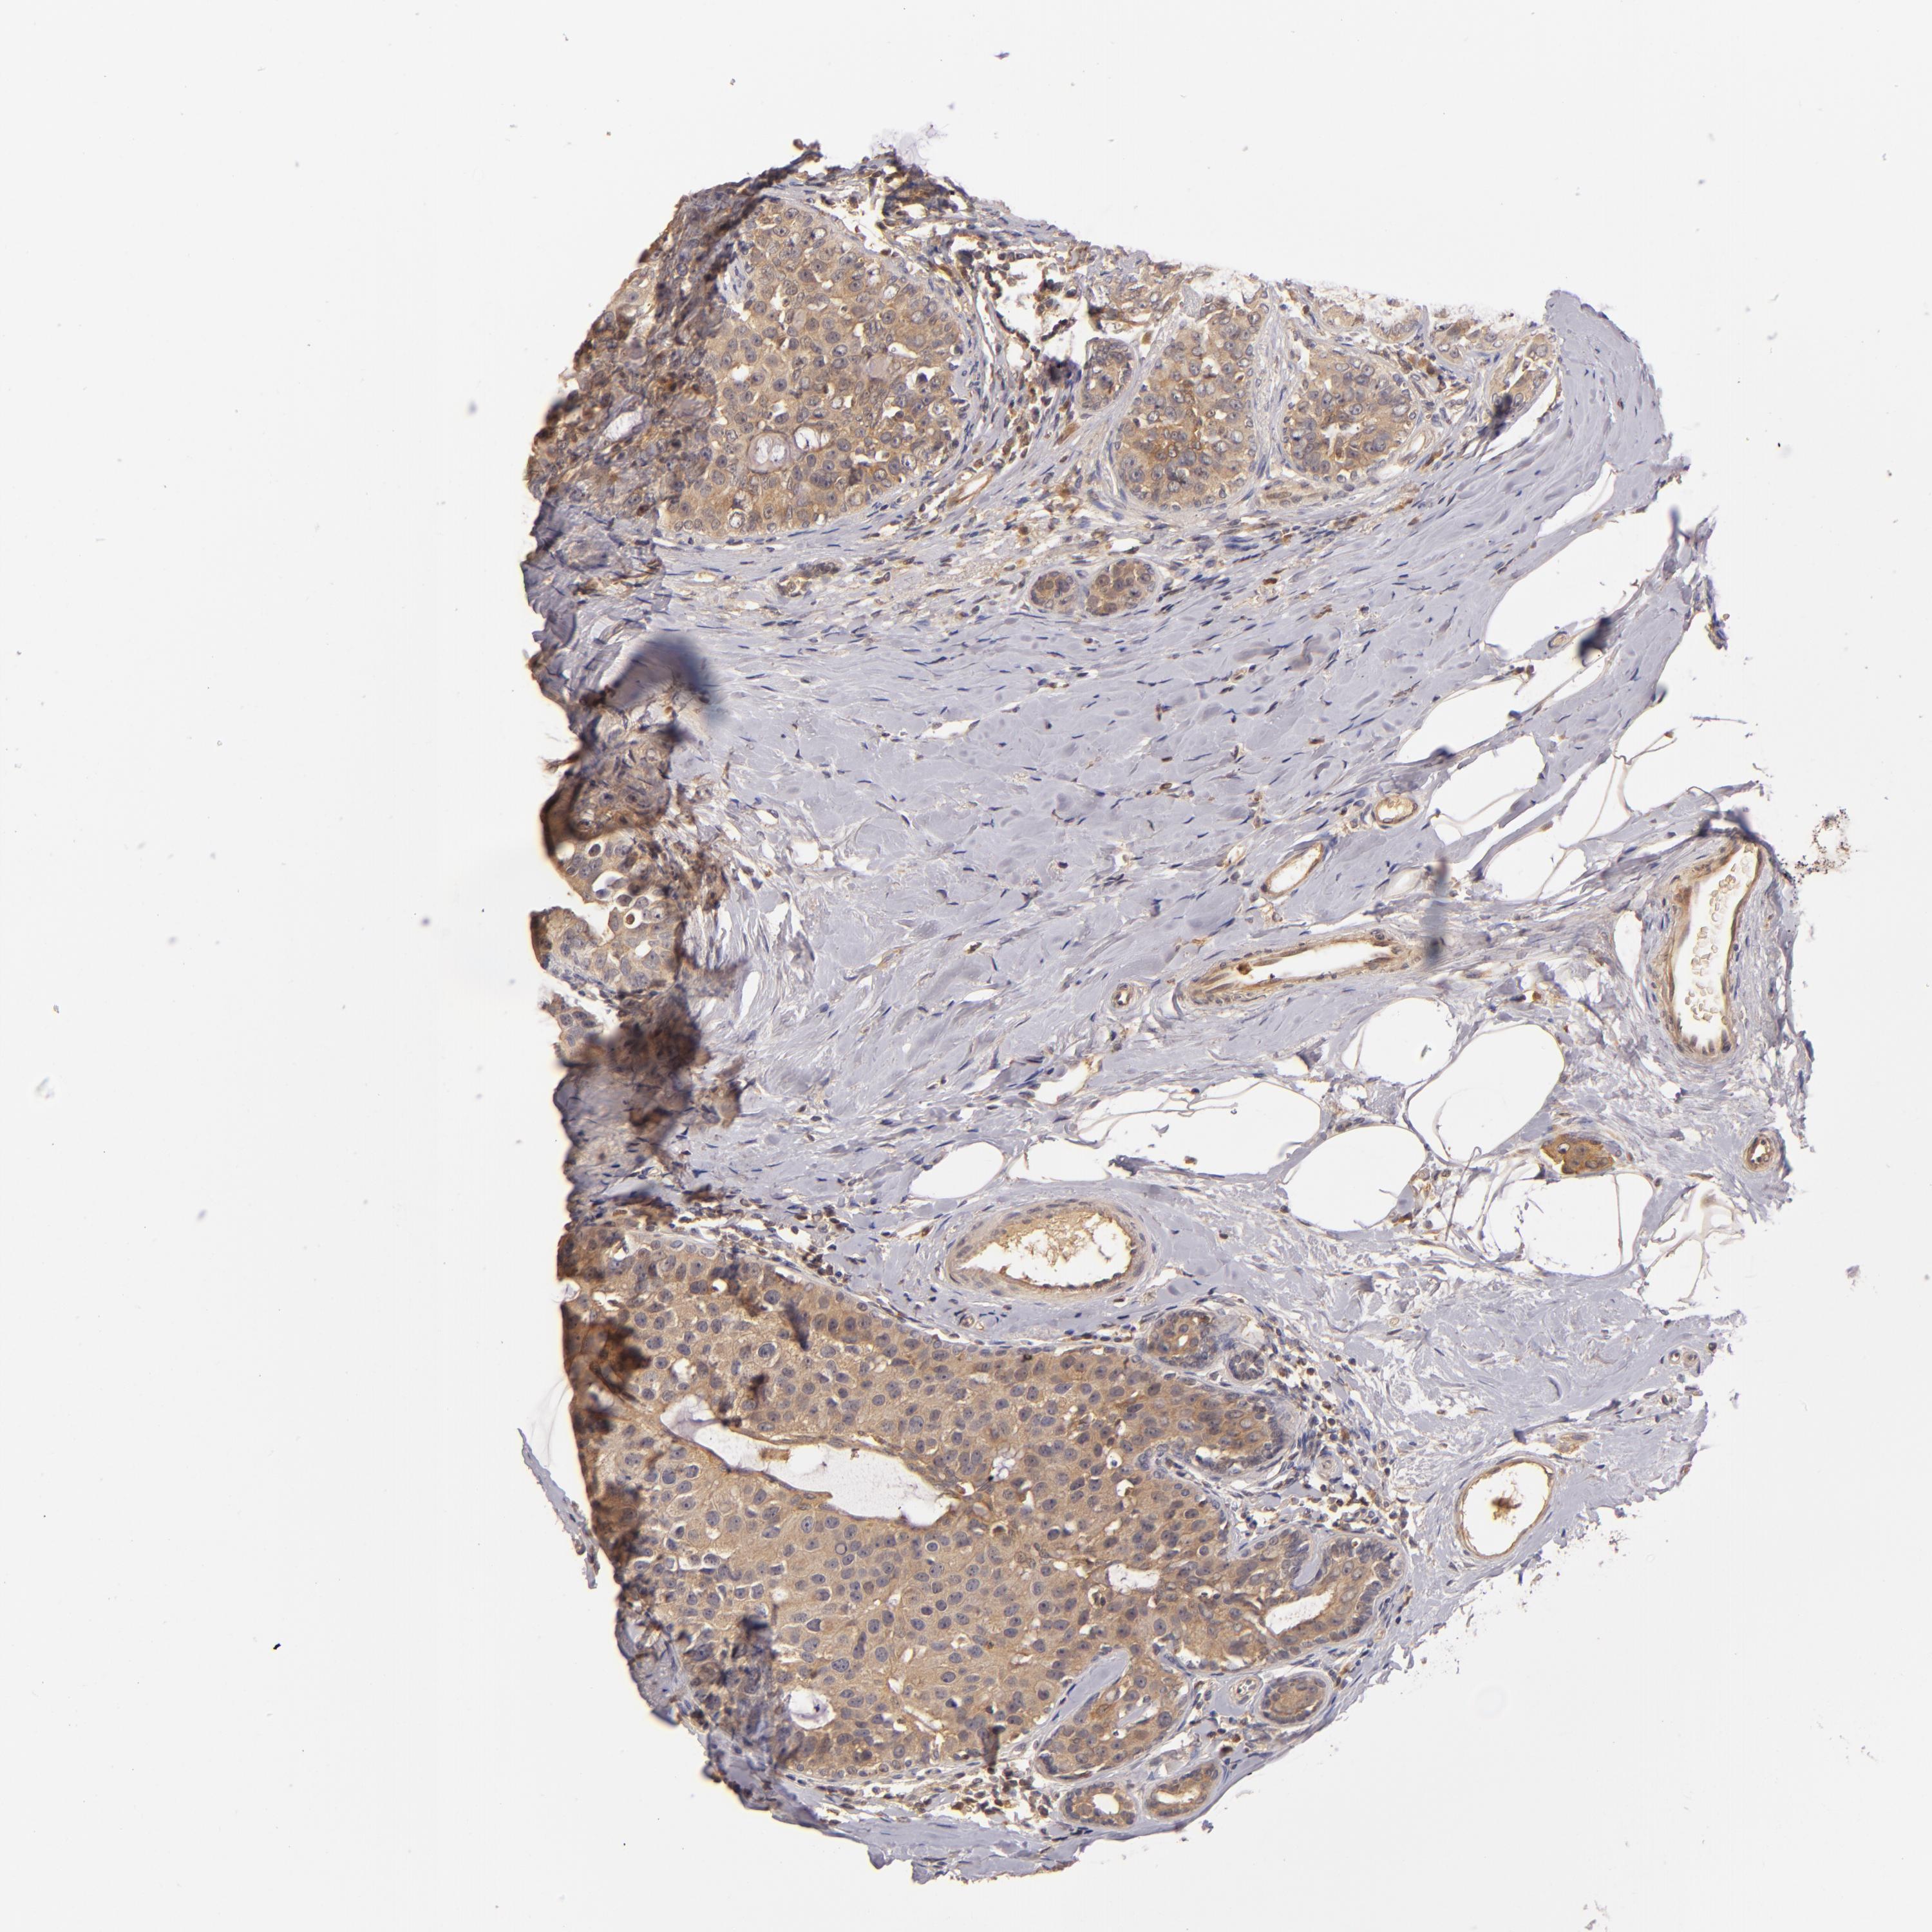

CANCER BREAST CANCER Show tissue menu

BRCA TCGA BRCA VALIDATION PROTEIN EXPRESSION